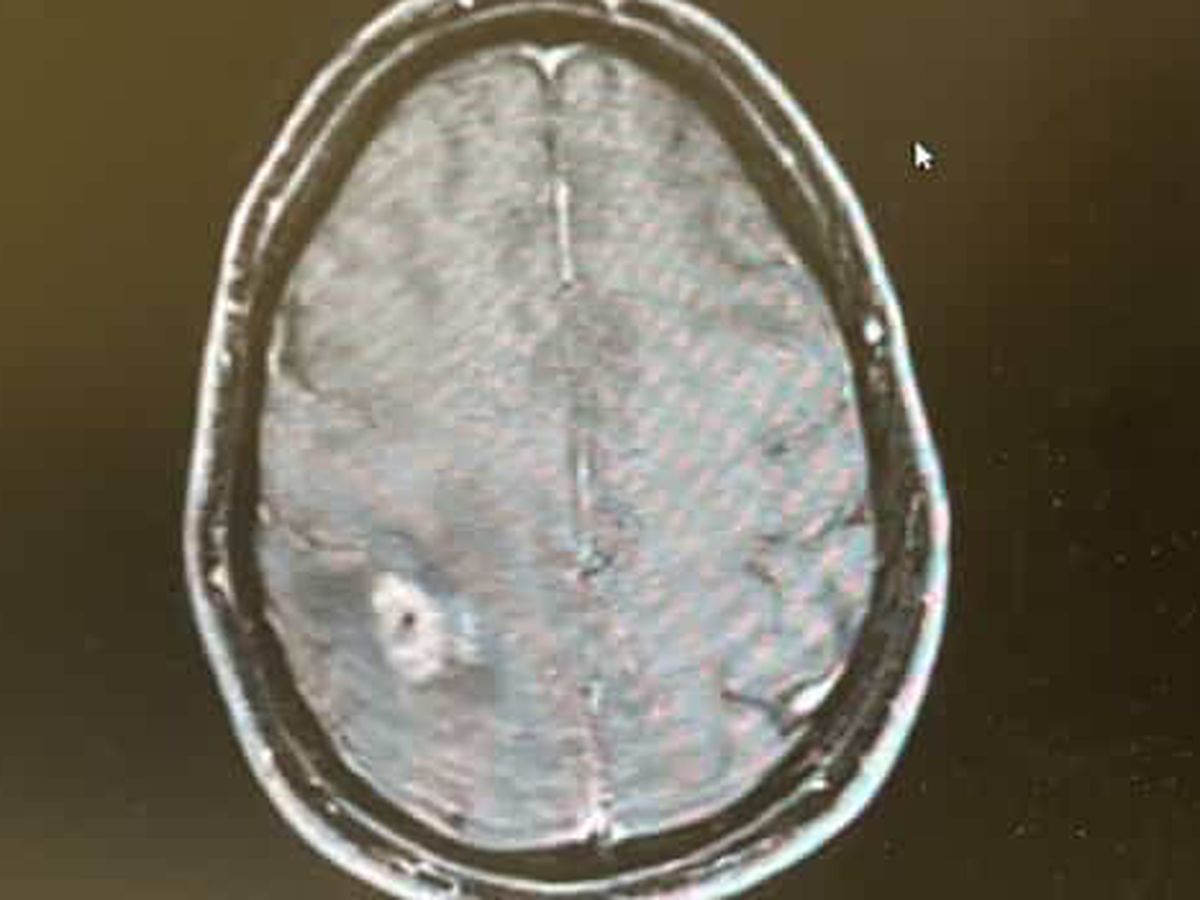

After months of being ignored and dismissed - on November 20, 2025, I had two focal seizures and finally got the news nobody wants. I have a brain tumor that needs removal ASAP.

So, on December 8, 2025, my amazing neurosurgeon at Mass General Hospital will literally crack my skull and try to evict this mutant in my head.

Unfortunately, even with this, my prognosis could be as little as two years. This tumor could be partially removed, but it will return. It is on my motor belt, so I am already partially paralyzed on my left side.